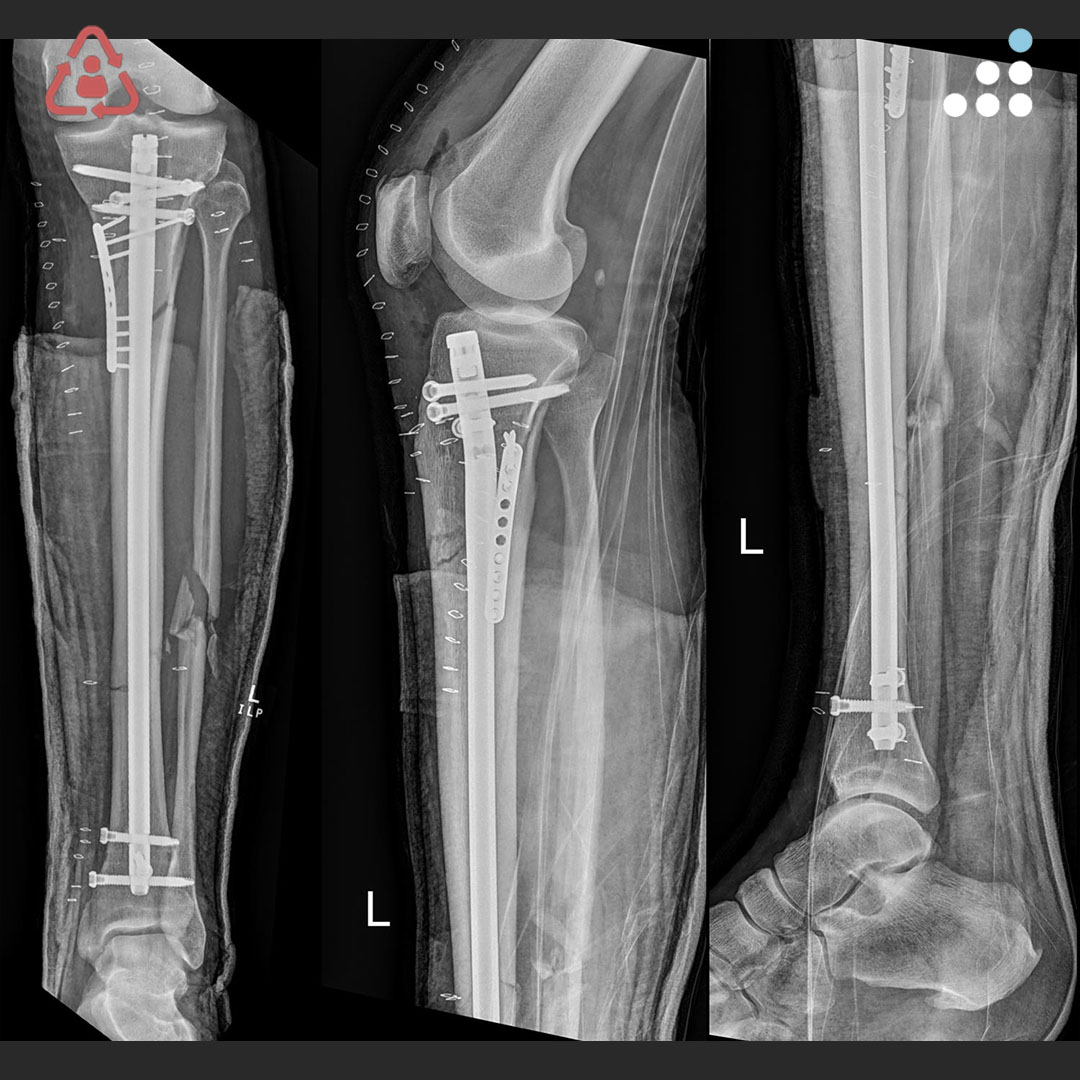

Here is a new case by Dr. Simon Donald and Queensland Health Bundaberg Hospital (@qldhealth). PROXIMAL SEGMENTAL TIBIAL FX S/P MALREDUCED IMN IN 58M How would you manage this #orthotwitter? Vote on this case for CME: orthobullets.tiny.us/4z6wm3rx